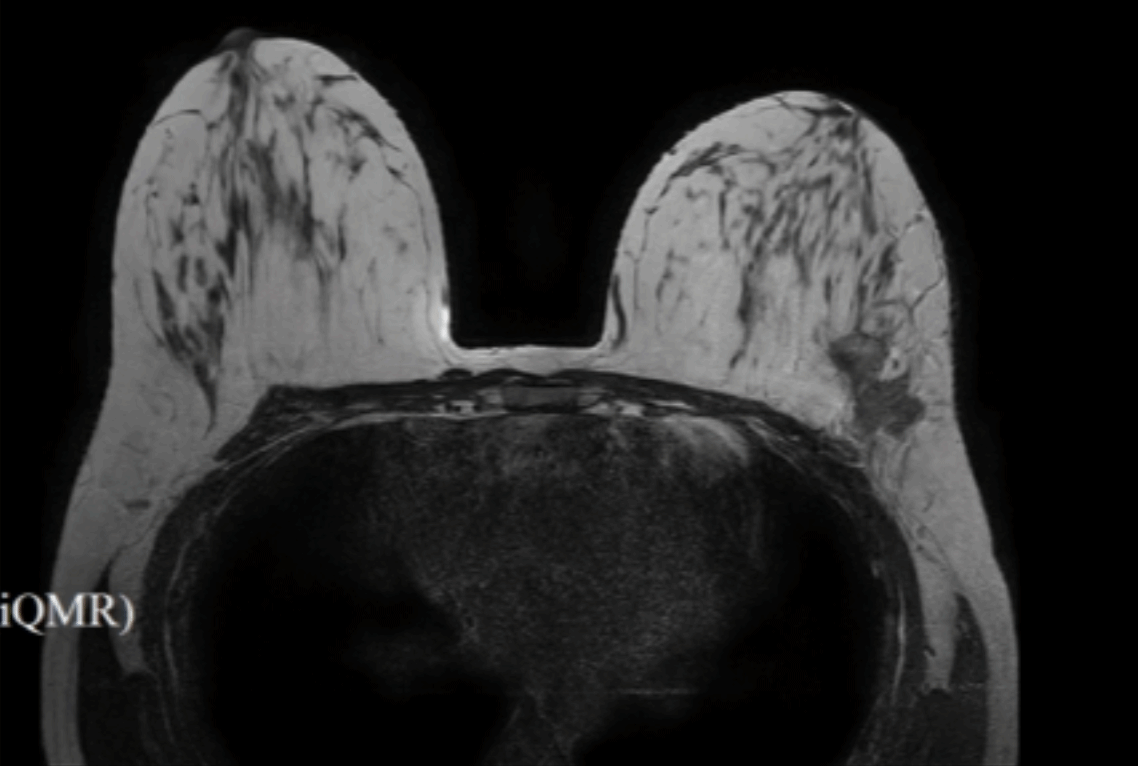

经过6个周期的规范治疗,影像学评估显示肿瘤明显缩小,达到手术指征。然而,小木巨大的乳房体积为手术带来了额外挑战:传统开放手术切口长、创伤大、恢复慢;而对巨大乳房进行即刻重建,在术野暴露、皮瓣处理、假体放置及对称性把控方面技术难度极高。

近日,手术如期进行。团队巧妙利用腋窝下隐蔽切口,将腔镜设备和精细器械置入皮下组织层。借助高清腔镜系统的放大视野,医生精准、完整地切除了左侧全部乳腺组织,并彻底清扫了腋窝淋巴结。随后,团队充分利用巨大乳房原有的充足皮肤和组织量,精细剥离并构建合适“口袋”,成功植入了定制的395CC乳房假体。腔镜技术保障了深层组织操作的精准与安全,有效减少了术中出血和组织损伤。尽管难度巨大,整个手术历时3小时顺利完成,患者生命体征平稳。